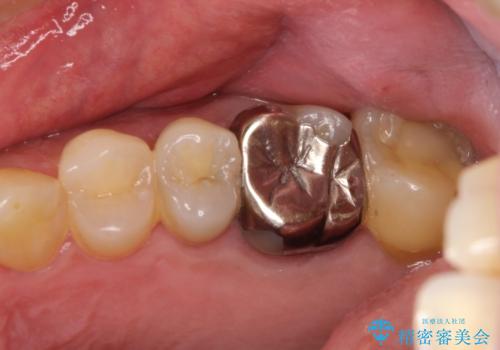

金属をセラミックにしたい、根管治療も行ったケース

奥歯の目立つ銀歯を白くしたい